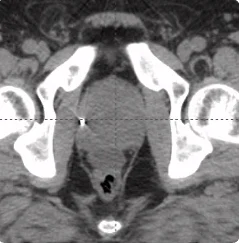

215 cc prostate post-CT showing BioProtect Balloon Spacer, prostate, and rectum.

Post-CT

Image courtesy of Dr. Shawn Zimberg, Radiation Oncologist.